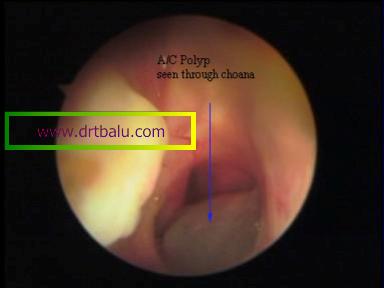

Choanal component of antrochoanal polyp

Postnasal examination will show the polyp if extending posteriorly at the level of choana. If it fills up the nasopharynx it will be visible there.